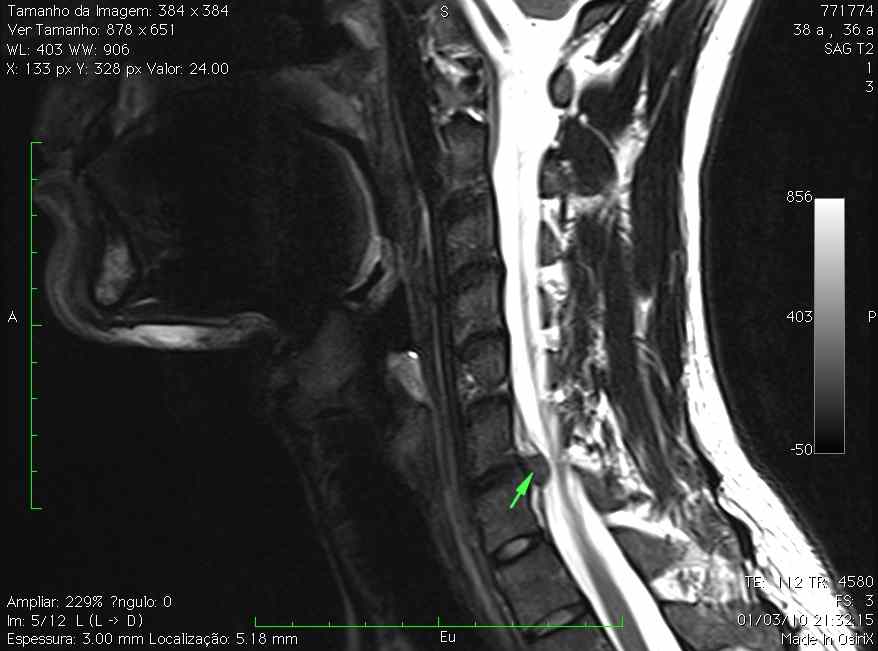

Hérnia discal cervical extrusa.

Imagem de ressonância magnética da coluna cervical com identificação de discopatia cervical com extrusão de conteúdo discal.